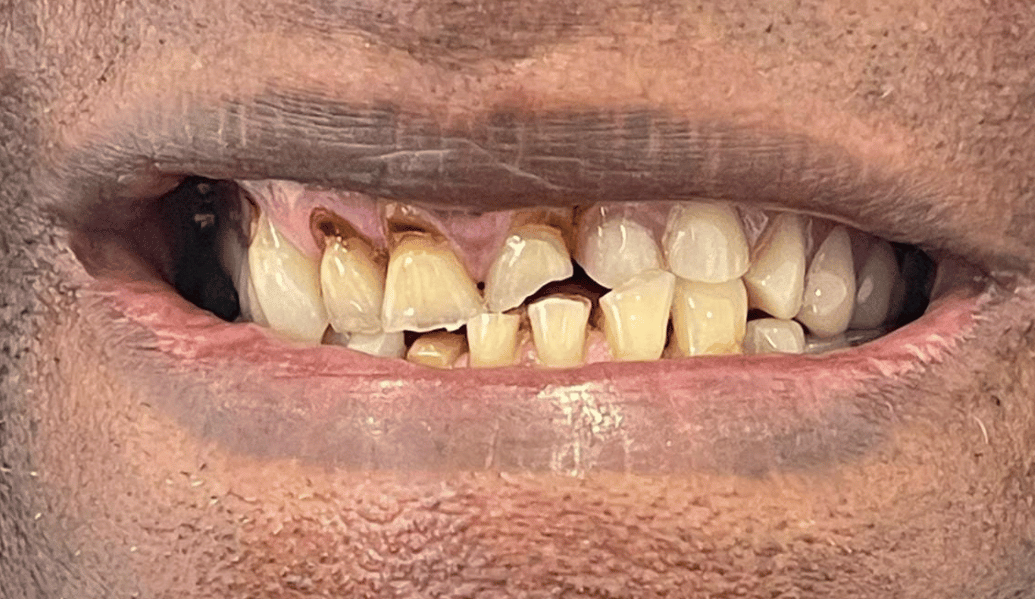

learn moreDental implants and us – together we can recreate a naturally beautiful smile.